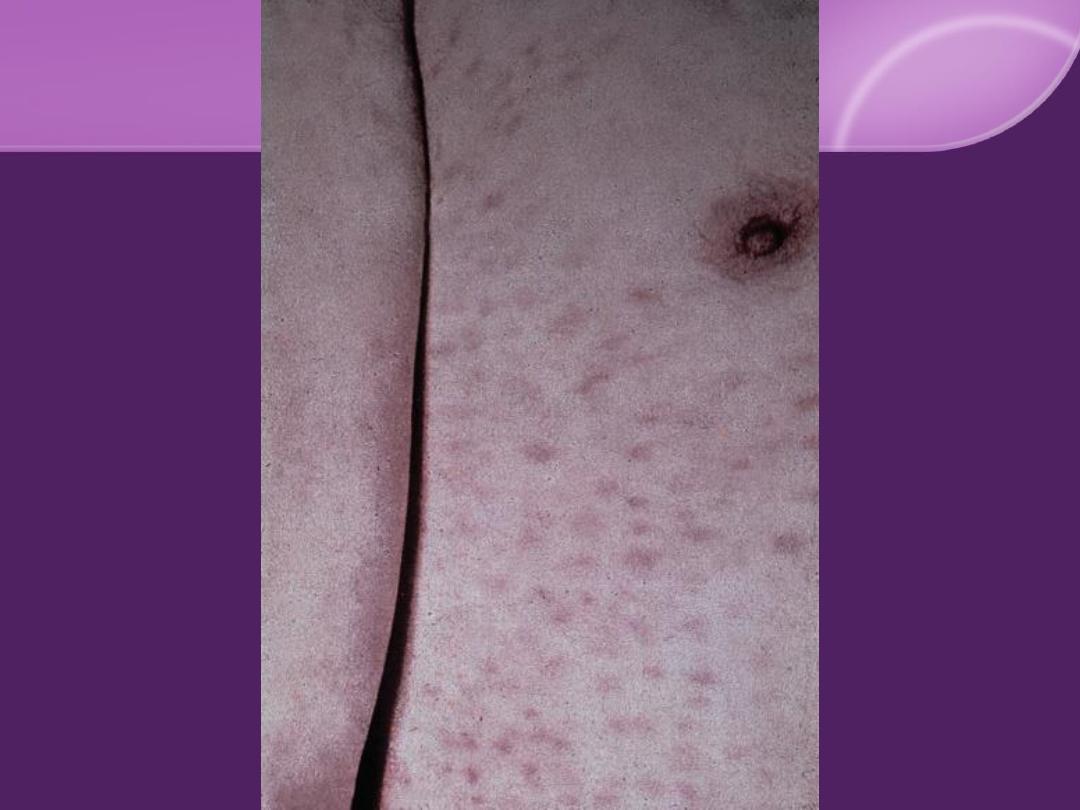

Secondary Syphilis:

Cutaneous Findings:

Flulike symptom and generalized painless

LN in 50%

DDX of Secondary Syphilis:

Great Imitator

Skin eruption

: pityriasis rosea, guttate

psoriasis, lichen planus, pityriasis versicolor,

drug eruptions, and viral eruptions.

1.

Little or no fever at onset.

2.

Pain or itching is minimum or absent.

3.

Lesions are non inflammatory, develop

slowly.

4.

Marked tendency to polymorphism.

5.

Bilateral symmetrical, with characteristic

palms and soles involvement.

6.

The color is characteristic, resembling a

"clean-cut ham" (coppery tint).